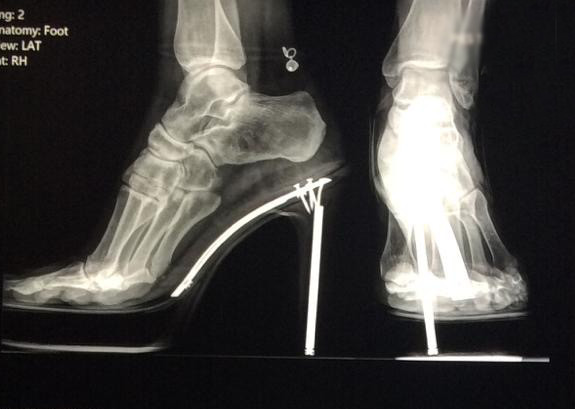

Radiología Digital como Herramienta Complementaria en el Dictamen de Bienes Muebles

Desde el descubrimiento de los rayos “X” y las placas radiográficas por Wilhelm Conrad Roentgen y su posterior difusión a través de la Asociación Físico médica de Wurzburg el 28 de diciembre de 1895, que fue la primera asociación que habló de los nuevos rayos que podían penetrar el cuerpo y fotografiar los huesos, ha habido muchos cambios tanto en la forma de obtener, procesar e incluso en la forma de visualizar, manejar y almacenar las placas radiográficas.